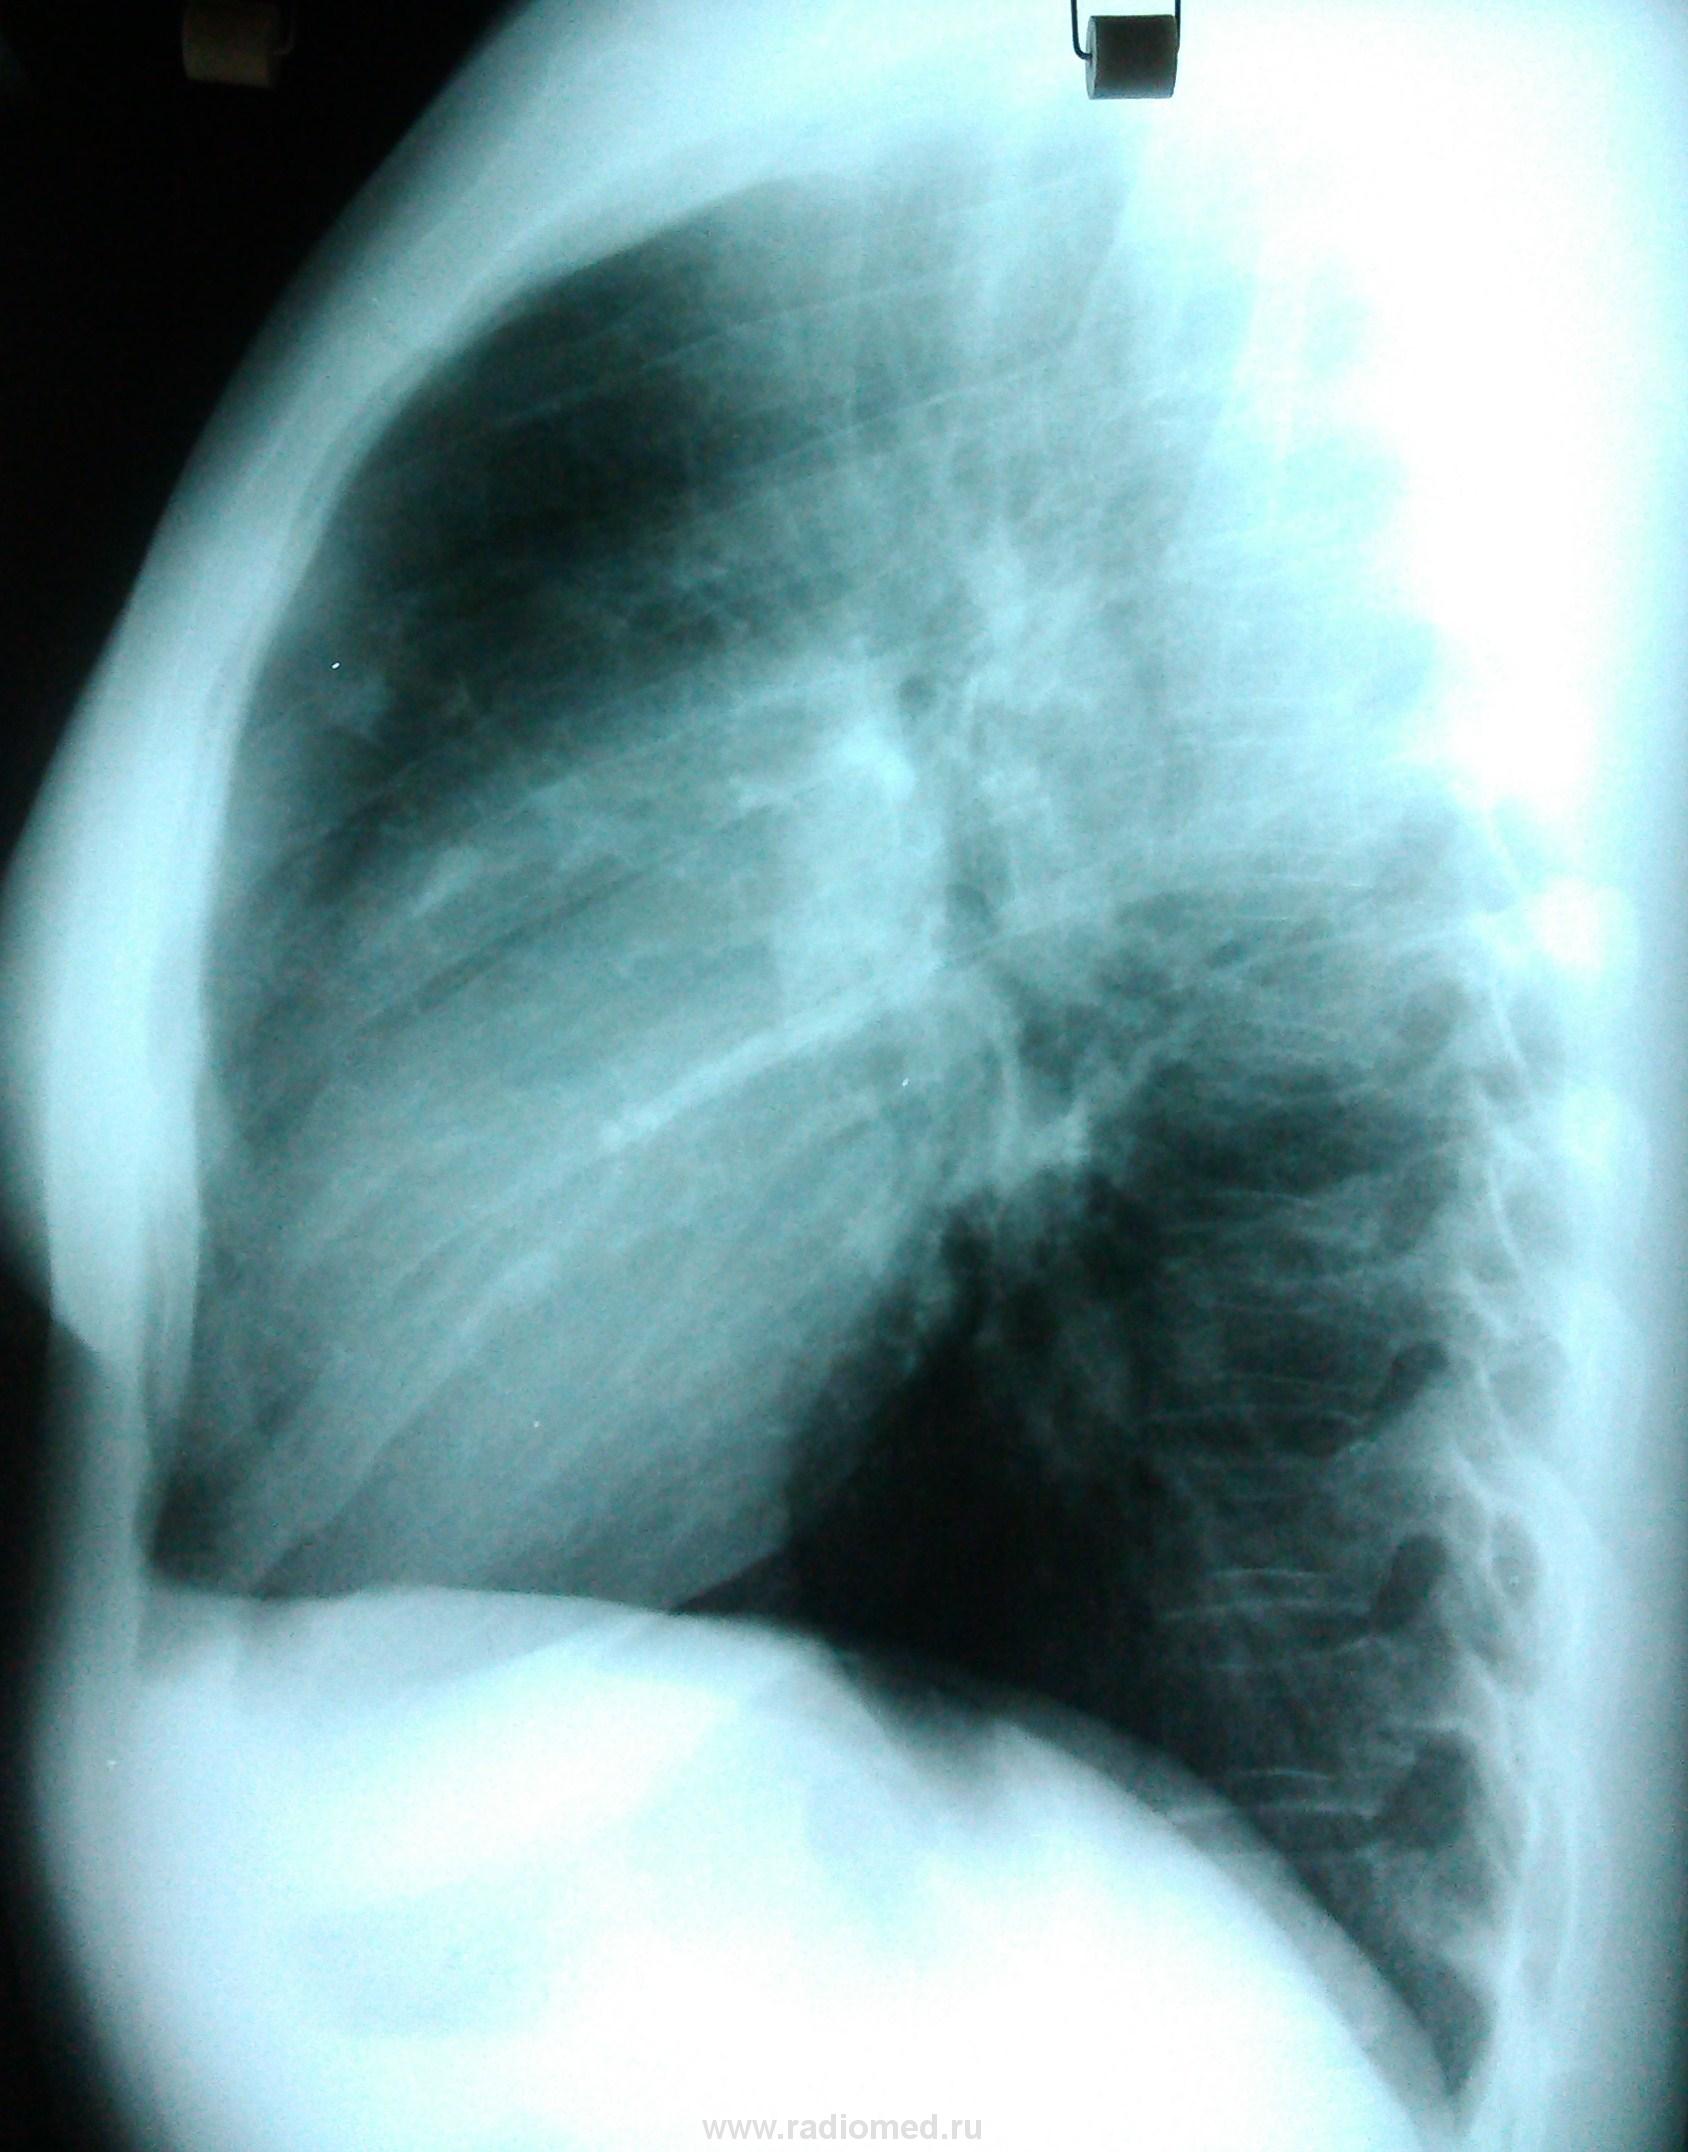

Сначала, в 11 году, был плотный очаг. К 2013 очевидно подрос, вполне может оказаться периферической опухолью.

Я опять за своё. Даже предположу, что не факт изображения на прямом и боковом одной и той же тени.

легочный аффект в S3 правого легкого с очередной вспышкой. Показано обследование в ПТД.

Петирфикат справа в S3 ( возможно в Sax )-если есть сомнения, возмите пациентку на R-скопию лёгких-определитесь с топографией изменённого участка ( имеет отношение к лёгочной ткани? какой сегмент ? и др.)

Периферический растет...

На боковом интересные "очаговые" тени...

Очаговые тени в переднем сегменте. В дифряд - мальформация.

Хотя бы нивелировать суммацию теней. На мой взгляд, прямая и боковая разнятся...

Прямая и боковая разнятся (на мой взгляд) за счет суммации изображений обоих легких на боковой рентгенограмме. При всем уважении к линейной ТГ - в конкретном случае (молодая женщина, визуальный рост "очага", относительно малые его размеры, три года наблюдения, доверие клиницистов к КТ) сразу постарался бы найти возможность для КТ.

Обработанные снимки.